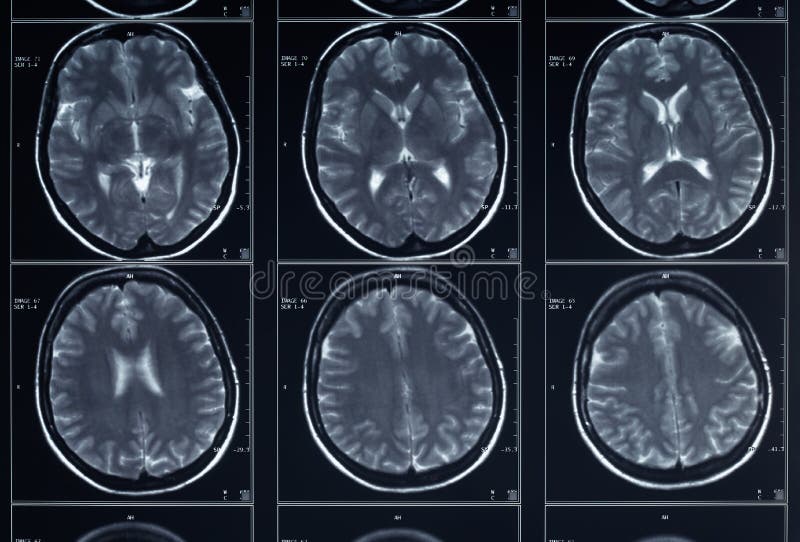

Risonanza Magnetica Rm Nelle Malattie Neurologiche Malattie Neurologiche Manuali Msd Edizione Professionisti

Risonanza Magnetica Con E Senza Contrasto Come Funziona Ed Effetti Collaterali Medicina Online

Risonanza Magnetica Encefalo Medical Imaging Caserta

Rm Risonanza Magnetica

Risonanza Magnetica Encefalo A Cosa Serve Radiologia Italia

Atlante Di Resonanza Magnetica Del Cervello